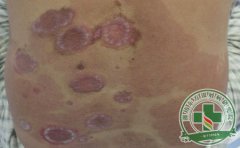

牛皮癣是一种常见的慢性皮肤疾病,许多人对它的扩散问题非常,担心牛皮癣会扩散导致身上牛皮癣症状...【详细】